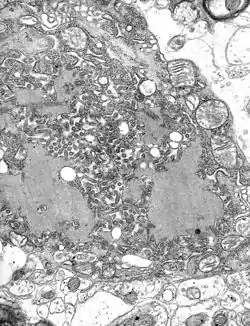

After a typical human infection by bite, the virus enters the peripheral nervous system. It then travels along the nerves towards the central nervous system by retrograde axonal transport. During this phase, the virus cannot be easily detected within the host, and vaccination may still confer cell-mediated immunity to prevent symptomatic rabies. Once the virus reaches the brain, it rapidly causes encephalitis and symptoms appear. This is called the "prodromal" phase and at this time, treatment is usually unsuccessful. Rabies may also inflame the spinal cord producing myelitis.